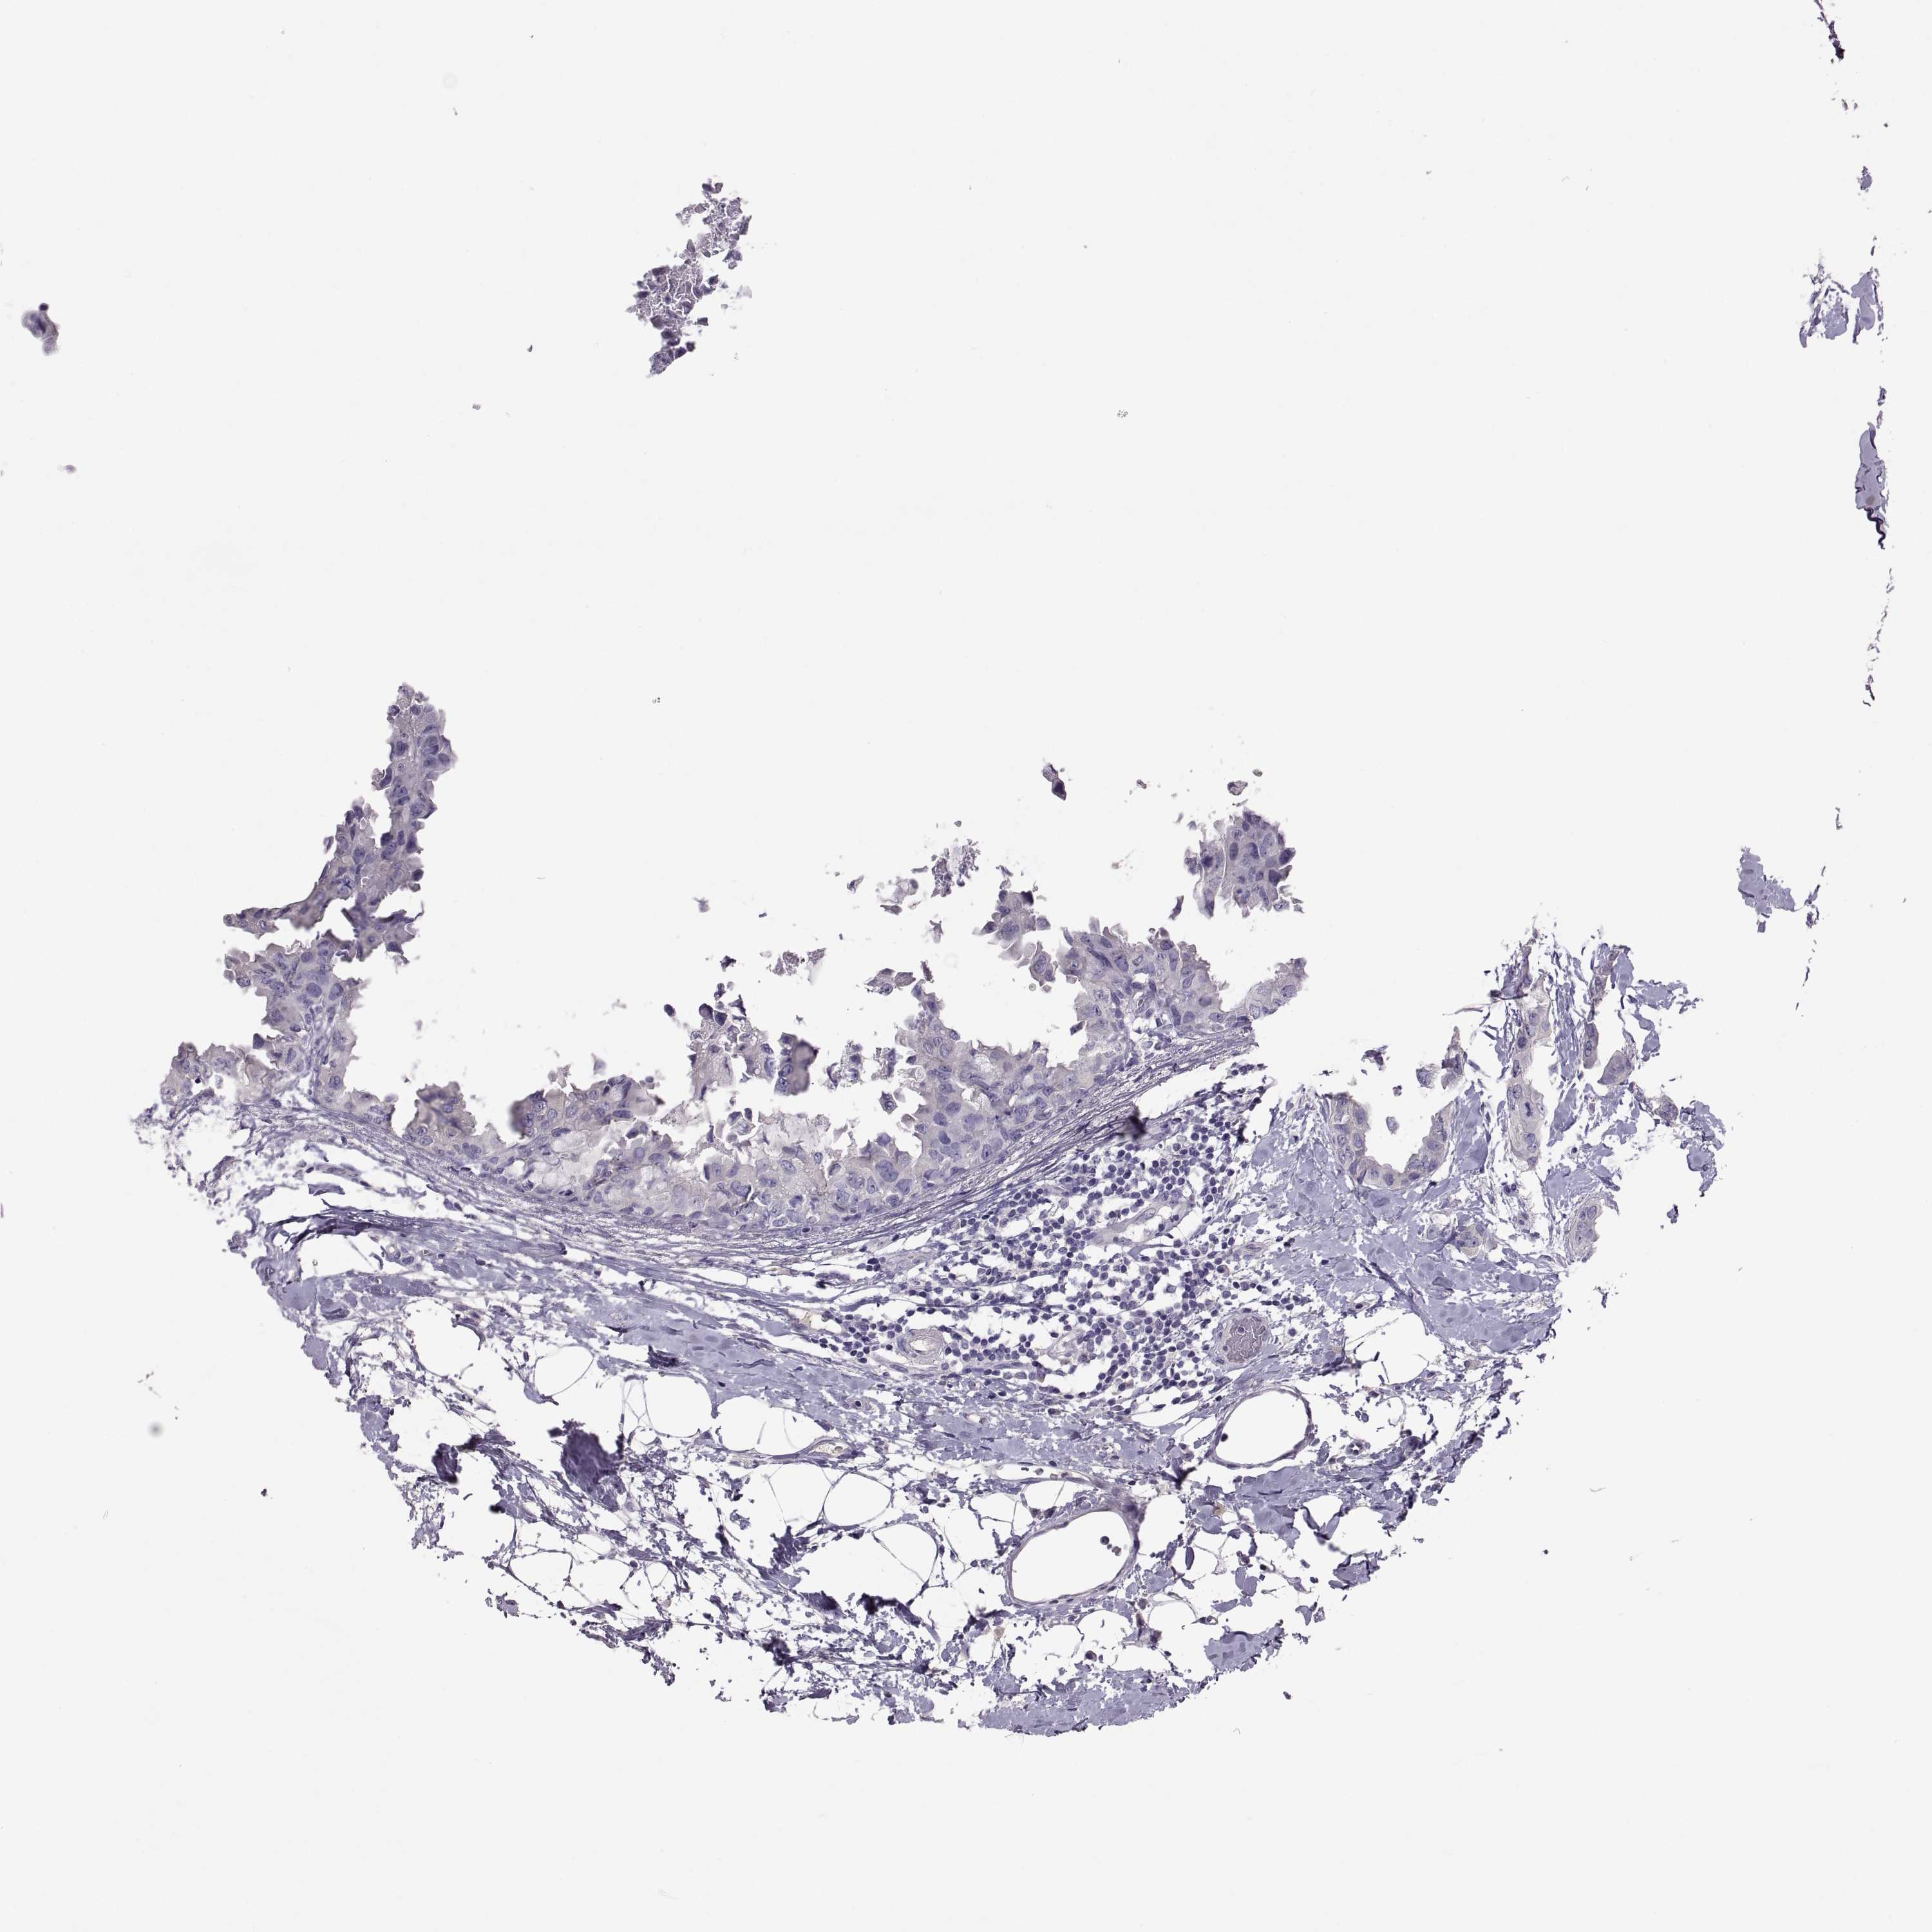

BRCA TCGA BRCA VALIDATION PROTEIN EXPRESSION

Breast cancer

Human cancer